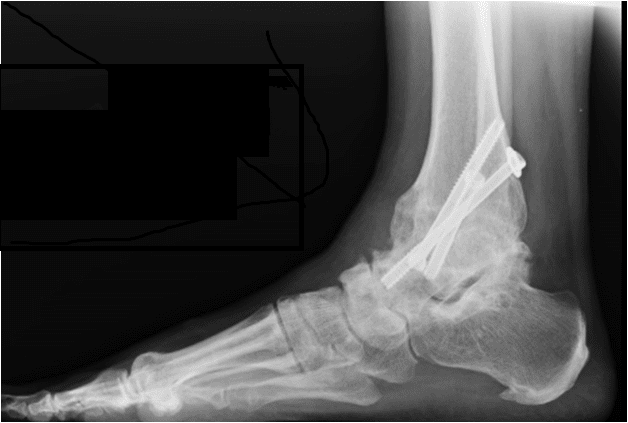

כיצד מתבצע ניתוח קיבוע מפרק קרסול? במהלך ניתוח קיבוע מפרק קרסול מתקנים את הזוויות של הקרסול או מגרדים את הסחוס כדי שיהיה חיבור טוב בין העצמות בעמדה טובה ומחברים אותם ע"י ברגים או פלטה. ברגע שהפרק מתמזג לעמדה טובה הברגים אינם נחוצים, אבל יוסרו רק לעתים נדירות.